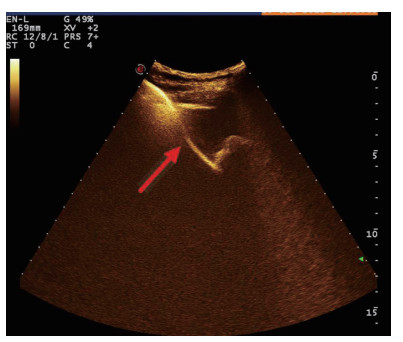

图 3 经引流管造影胆囊超声显像,二维图像(左),造影图像(右)

术后再次经肘静脉超声造影同时经引流管超声造影:PTGBD后,再次经肘静脉快速团注SonoVuel 2 mL,在造影成像模式下进行观察肝脏被膜、胆囊床穿刺路径有无造影剂外渗,腹腔内有无外渗凝聚的造影剂,判断有无活动性出血及出血程度,如判断出血速度快、出血量较大,考虑动脉性出血,及时改为开腹或腔镜手术止血。PTGBD术后经引流管超声造影,置管成功后快速抽出胆囊内残留胆汁,减轻胆囊压力后,在超声造影模式下直接经引流管注入配制待用的稀释声诺维造影剂20 mL,实时动态的观察造影剂在胆囊腔内的充盈范围(图 23),评估引流管的通畅程度及引流范围、观察其在胆囊腔内的位置走形及卷曲情况、观察胆囊周边及腹腔内有无造影剂外渗。如患者腹痛症状加剧,结合经引流管超声造影判断有胆汁漏出表现,应持续监测观察患者生命体征及保守治疗效果,必要时及时改行开腹或腔镜手术治疗。

超声造影是利用超声造影剂微泡(本组应用的是声诺维超声造影剂微泡)在低机械指数声波照射下发生共振,产生线性及非线性谐波回声信号,形成造影增强图像的技术,是近年来新兴的超声技术,具有实时、可连续观察、无辐射、可重复性好、毒不良反应少等优势,为临床提供了全新的诊疗手段[14]。经肘静脉注入的标准配置超声造影剂是一种血池造影剂,可以反映组织的血流灌注情况同时亦被广泛应用于肝、脾、肾等实质性脏器破裂的诊断,其诊断的敏感性及特异性均明显优于二维超声,且与增强CT有较好的一致性[15-16]。本组病例术前经肘静脉注入标准配置造影剂后,胆囊壁均显影增强,胆囊穿孔及周边积液处表现为造影无充盈区,穿刺置管后再次静脉路超声造影,迅速发现术后出血部位且可敏感评估是否为活动性出血(经手术证实)。除1例因活动性出血中转腹腔镜手术外,其余32例置管成功后经引流管口注入稀释造影剂20 mL(1:200稀释),评价引流管位置、引流范围及是否出现胆汁外漏取得良好效果,所有引流导管均能够清晰显示引流导管置入路径、引流管形态及引流范围,引流管置入恰当者,头端位于胆囊内,全管显影清晰,造影剂弥散区域与胆囊大小吻合; 置管后胆汁漏出者,可见造影剂沿引流管周边渗出[17-18],本组中3例出现造影剂外渗,其中两例渗出范围局限于胆囊床附近,未渗出至游离腹腔,患者腹痛症状稍有加剧,经胆囊减压及对症处理后好转,其中1例见造影剂渗出至肝肾间隙,患者腹痛症状加剧明显,考虑置管位置不当,余行急诊腹腔镜手术治疗,术中证实为系膜胆囊,且可见引流管侧孔部分外露。笔者的经验是,术前选择静脉路超声造影有助于对胆囊情况的评估及穿刺点的选择,术中正确选择穿刺针的入路有利于提高穿刺引流的成功率。首先是胆囊穿刺部位的选择应选择在靠近胆囊颈侧,此处胆囊位置比较固定,受体位影响较小,且胆囊床结缔组织较为固定,有助于将漏出胆汁包裹局限,其次是进针方向与胆囊床尽可能保持垂直,减少进针位置的偏移,同时置管成功后应即刻尽量抽尽胆囊内的感染性胆汁,生理盐水冲洗后行经引流管稀释超声造影有助于判断置管位置、引流范围及是否出现胆汁漏出,减少不必要的并发症发生率。穿刺引流后可以根据患者的营养状况待窦道形成稳定后择期拔除引流导管。对全身情况改善适合手术治疗且有手术意愿者可以考虑择期胆囊切除术。